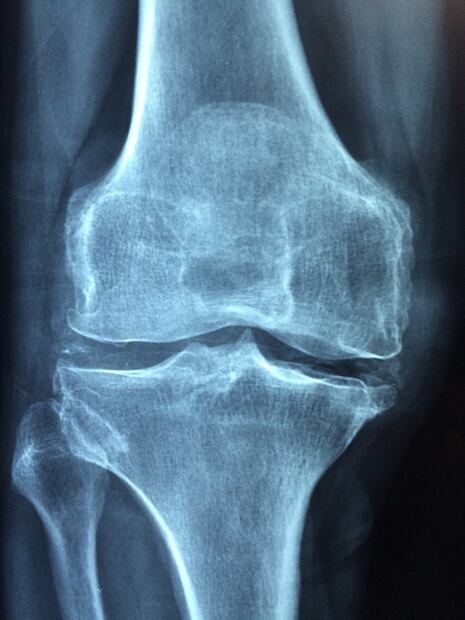

En este marco, uno de los temas de salud que más estudios ha demandado es la osteoporosis, una enfermedad que hace que los huesos se debiliten y se vuelvan frágiles, en tal medida que una caída o hasta una leve tensión, como agacharse o toser, pueden causar una fractura, según precisiones del Instituto Mayo Clinic.

Según este estudio, existe una proteína que previene la osteoporosis. Se trata en realidad de un gen codificante de proteína llamado Ctdnep1 que tiene la facultad de regenerar partes viejas de los huesos. En la revista Medicina y Salud Pública señalan que las investigaciones continuarán enfocadas en esta proteína como un posible aporte positivo en el abordaje terapéutico para prevenir la pérdida excesiva de fuerza en los huesos que causa la osteoporosis.